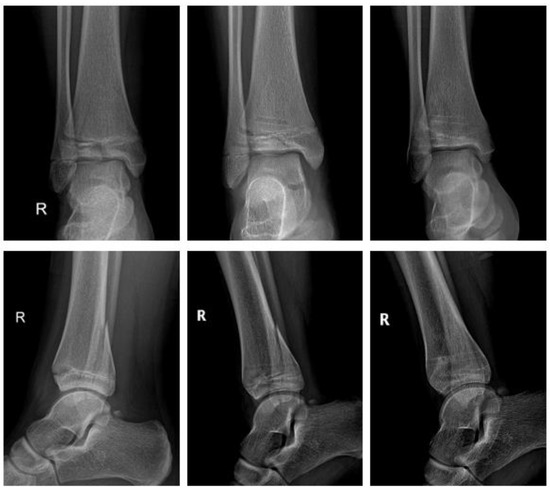

2.4.4. Fracture of the Ankle